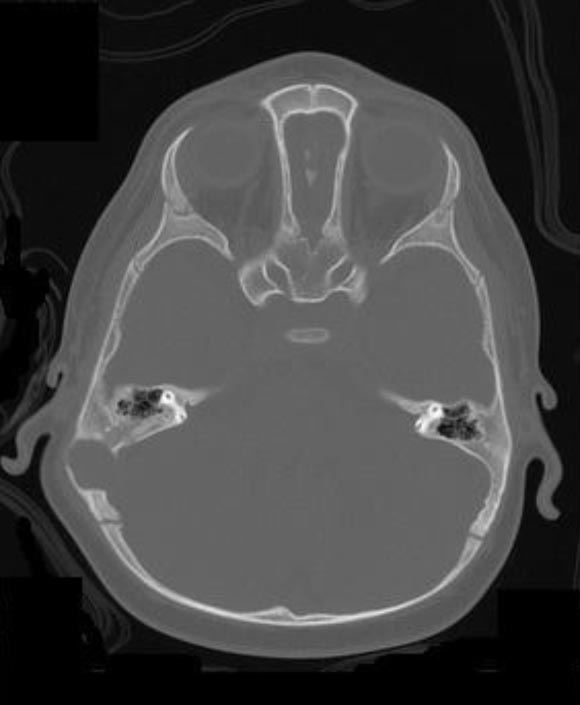

A questo punto viene eseguita una Risonanza Magnetica Nucleare (RMN) per definire l'eventuale coinvolgimento dell'encefalo: si documenta una lesione che determina un'ampia osteolisi a tutto spessore della teca cranica, giungendo a contatto con il cervelletto (Figura 1 e Figura 2). La Tomografia Computerizzata (TC) conferma il reperto (Figura 3).

Figura 3. Immagine TC con lesione osteolitica della teca cranica.